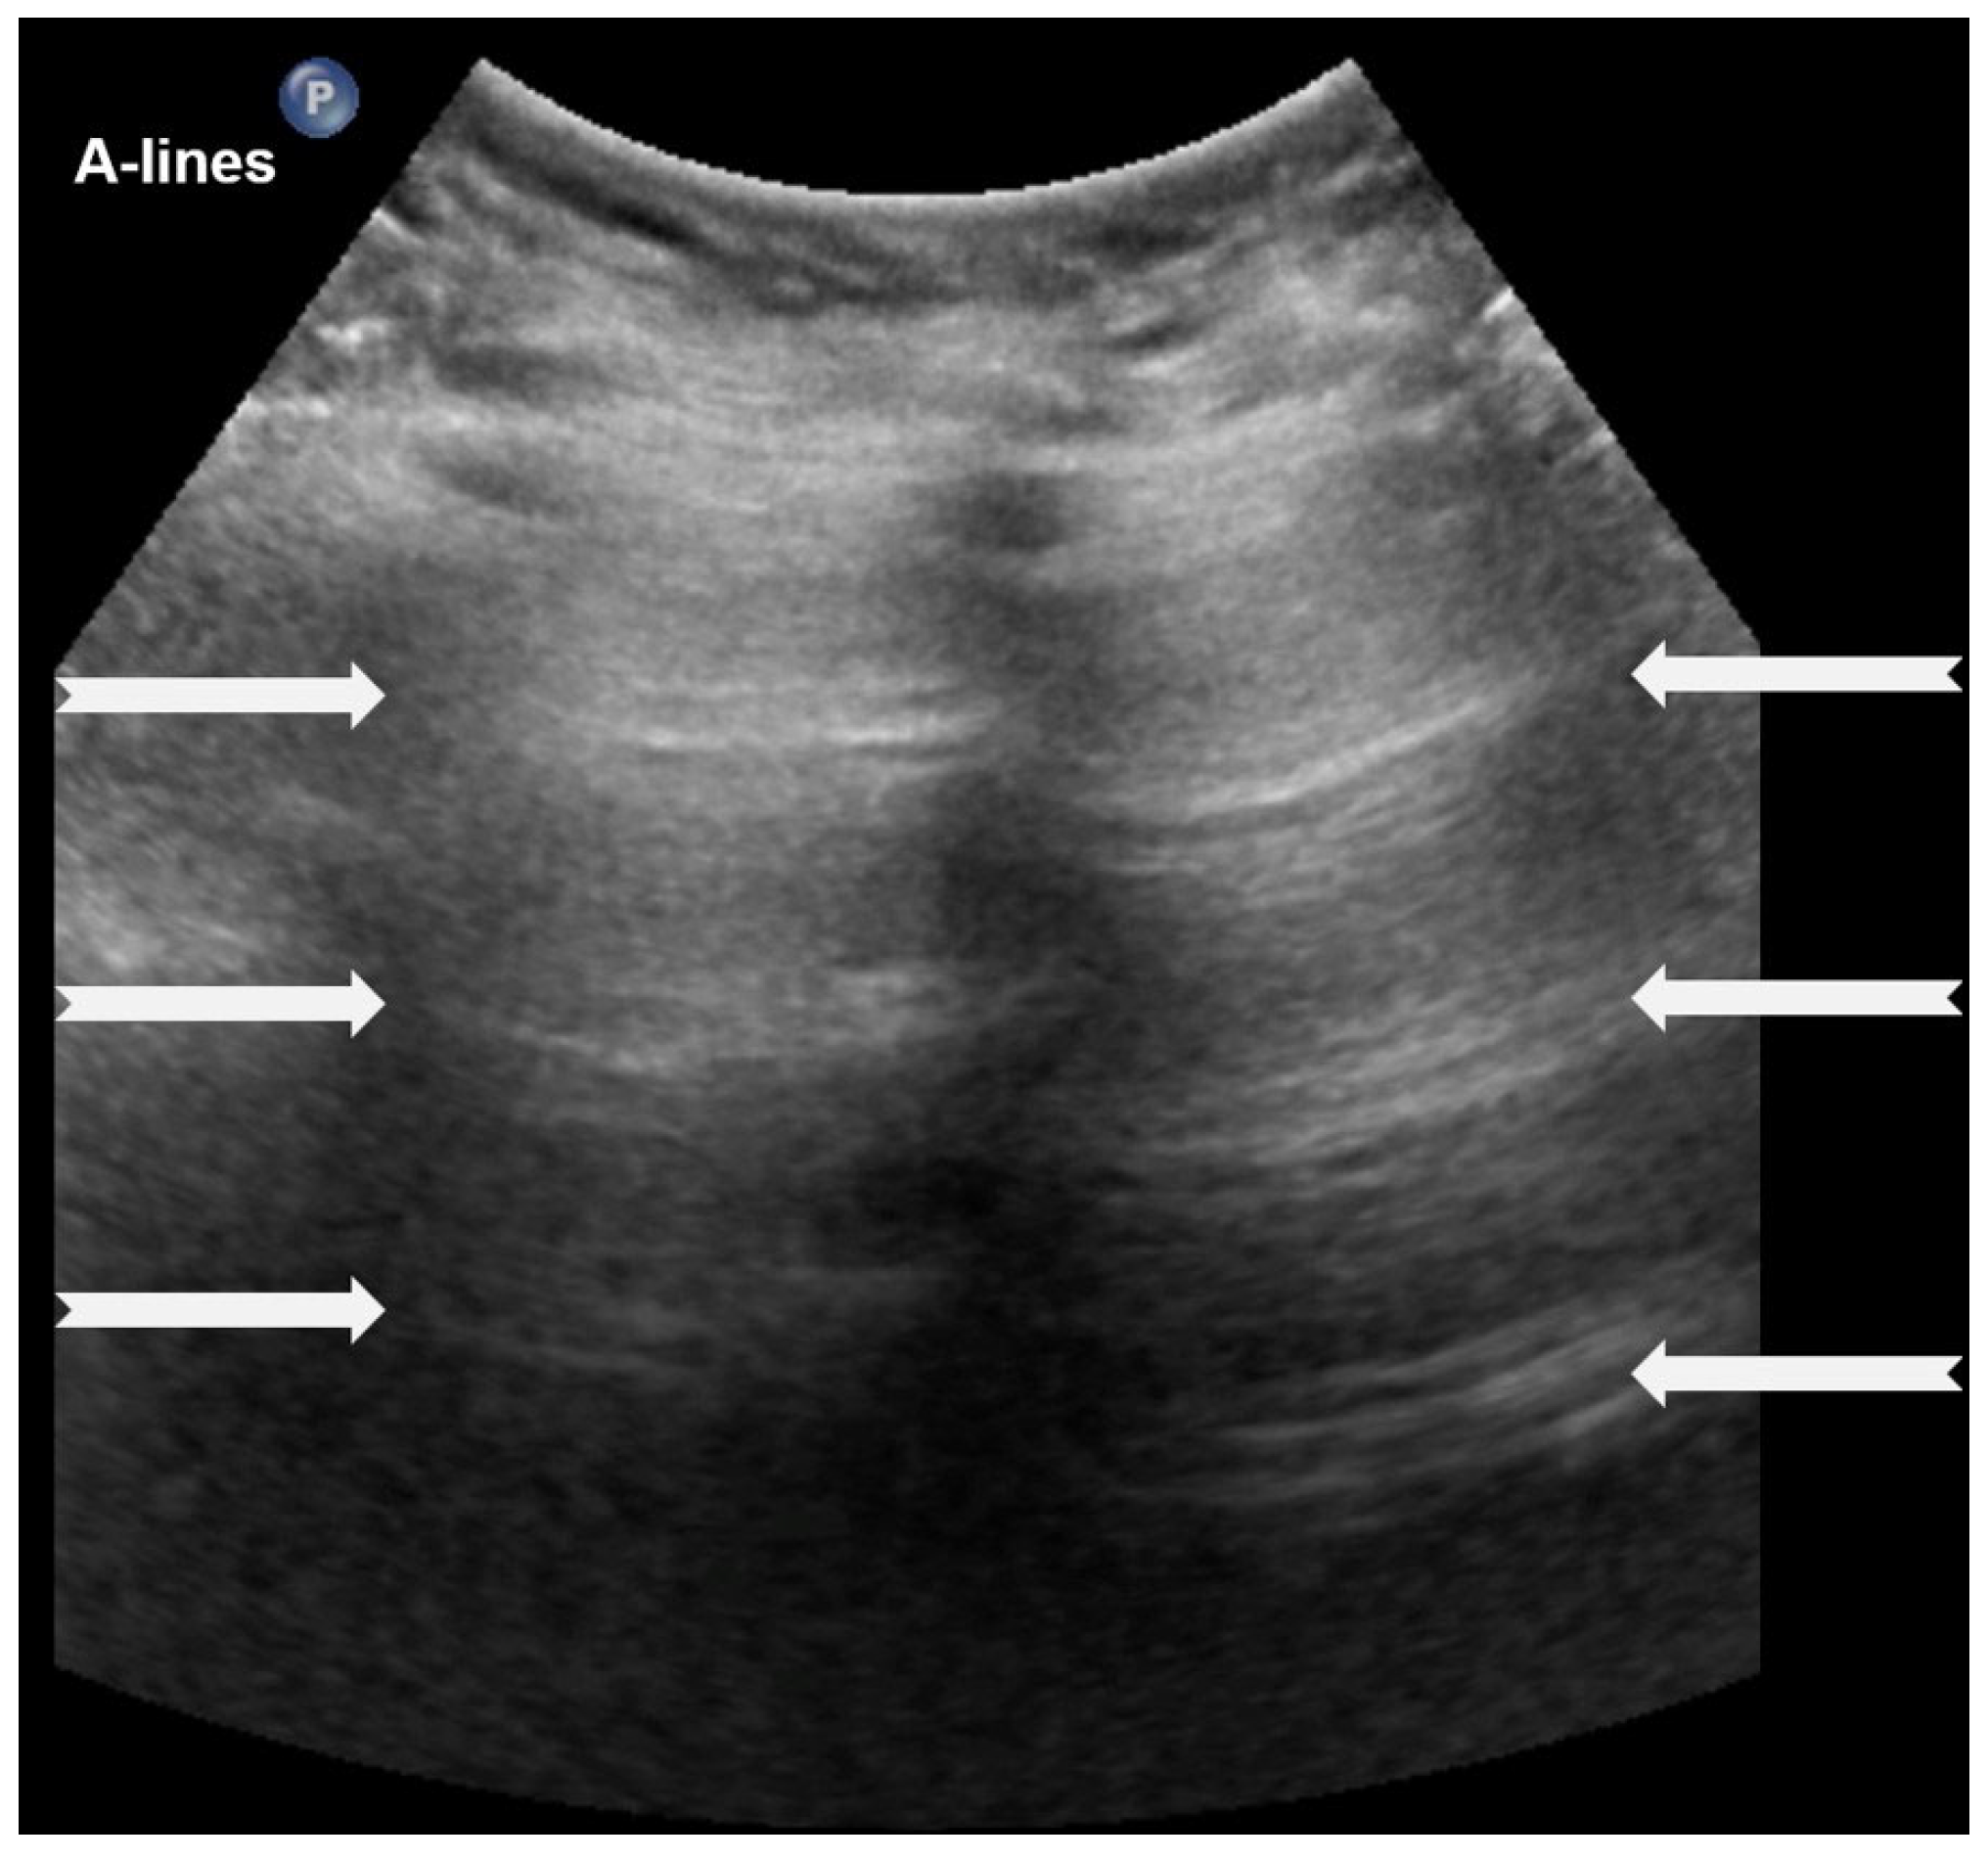

A-lines are horizontal, bright, echogenic lines that appear at equal intervals below the pleural line, running parallel to it (Figure 1). They are reverberation artifacts caused by the reflection of ultrasound waves between the pleura and the ultrasound probe. Although their presence typically indicates well-aerated, healthy lung tissue, A-lines can also be seen in certain pathological conditions, such as pneumothorax, where free air is present. Thus, A-lines are not always necessarily a sign of normal, healthy lungs [5,6,12,13,14,15,16].

Figure 1.

A-lines: Horizontal, bright, echogenic lines at equal intervals below the pleural line, running parallel to it. A-Lines are one of the main (basic) artifacts in LUS.